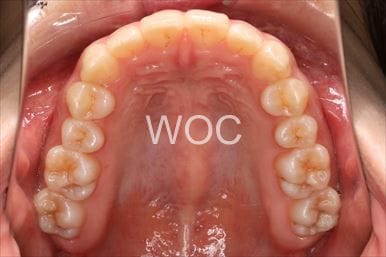

治療前4

治療後4